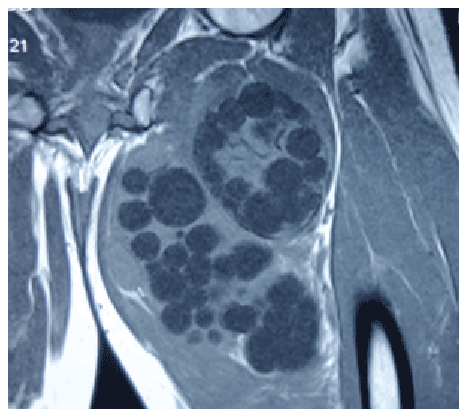

常规血液调查,腹部的超声波和胸部的X射线是正常的。该地区的超声显示多象肿胀。肿胀的FNAc显示出囊性病变,并报告为寄生或淋巴囊肿。在血清学试验中,用值为74.20 IU升高液体的IgG。大腿的MRI揭示了左大腿内膜肌肉舱中的多次大,多象型肿块。最大的囊肿的尺寸为83×69×103mm。看到多种可变的囊肿除以隔膜。没有发现明显的骨骼或关节参与图2. MRI特征旨在提示包发虫质量。

图2:核磁共振图像

MRI是首选的检查方式,因为它能够显示包虫囊肿的大部分特征,除了钙化。典型的MRI表现包括多囊性囊肿,T2加权图像上低强度边缘(边缘征)或膜脱落[8,9]。最典型的症状是大囊肿内存在子囊肿。“边缘征”可区分肝、肺内的水螅型囊肿与非寄生虫性囊肿。这代表寄生膜(生发层)和作为宿主反应的富含胶原的膜(包膜)。Comert等人首先将“睡兰征”描述为肌内包虫囊肿[10]的特征征,在所有t1加权图像上呈低信号的塌陷的寄生膜代表一个无法存活的囊肿,并将其描述为“蛇征或蛇征”[11]。